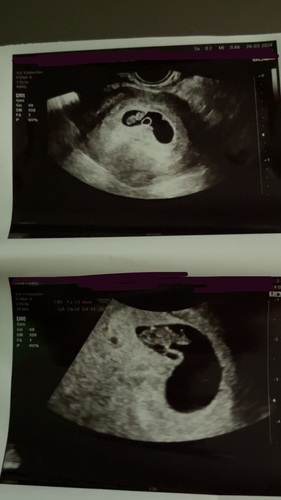

Ramzi en de nub was meisje dacht zelfs de verloskundig... alle kwaaltjes zijn ook meisje!

maar was toch echt n jongen!😂

Was de echo inwendig?

Ik weet het niet zeker hoor maar omdat jou beebje juist aan de andere kant zit denk ik dat😅

Ik moet wel zeggen dat mijn echo er met 6 weken anders uit zag..

Ze zeggen dat de placenta in de buurt van het embryo is , dus neig dan meer meisje . Maar ik weet het niet hoor

Ik heb gister een oudere echo van mijn dochter opgezet en merendeel reageert jongen en het is toch echt een meisje.. dus ik denk dat het niet klopt en de kans is natuurlijk maar 50/50.